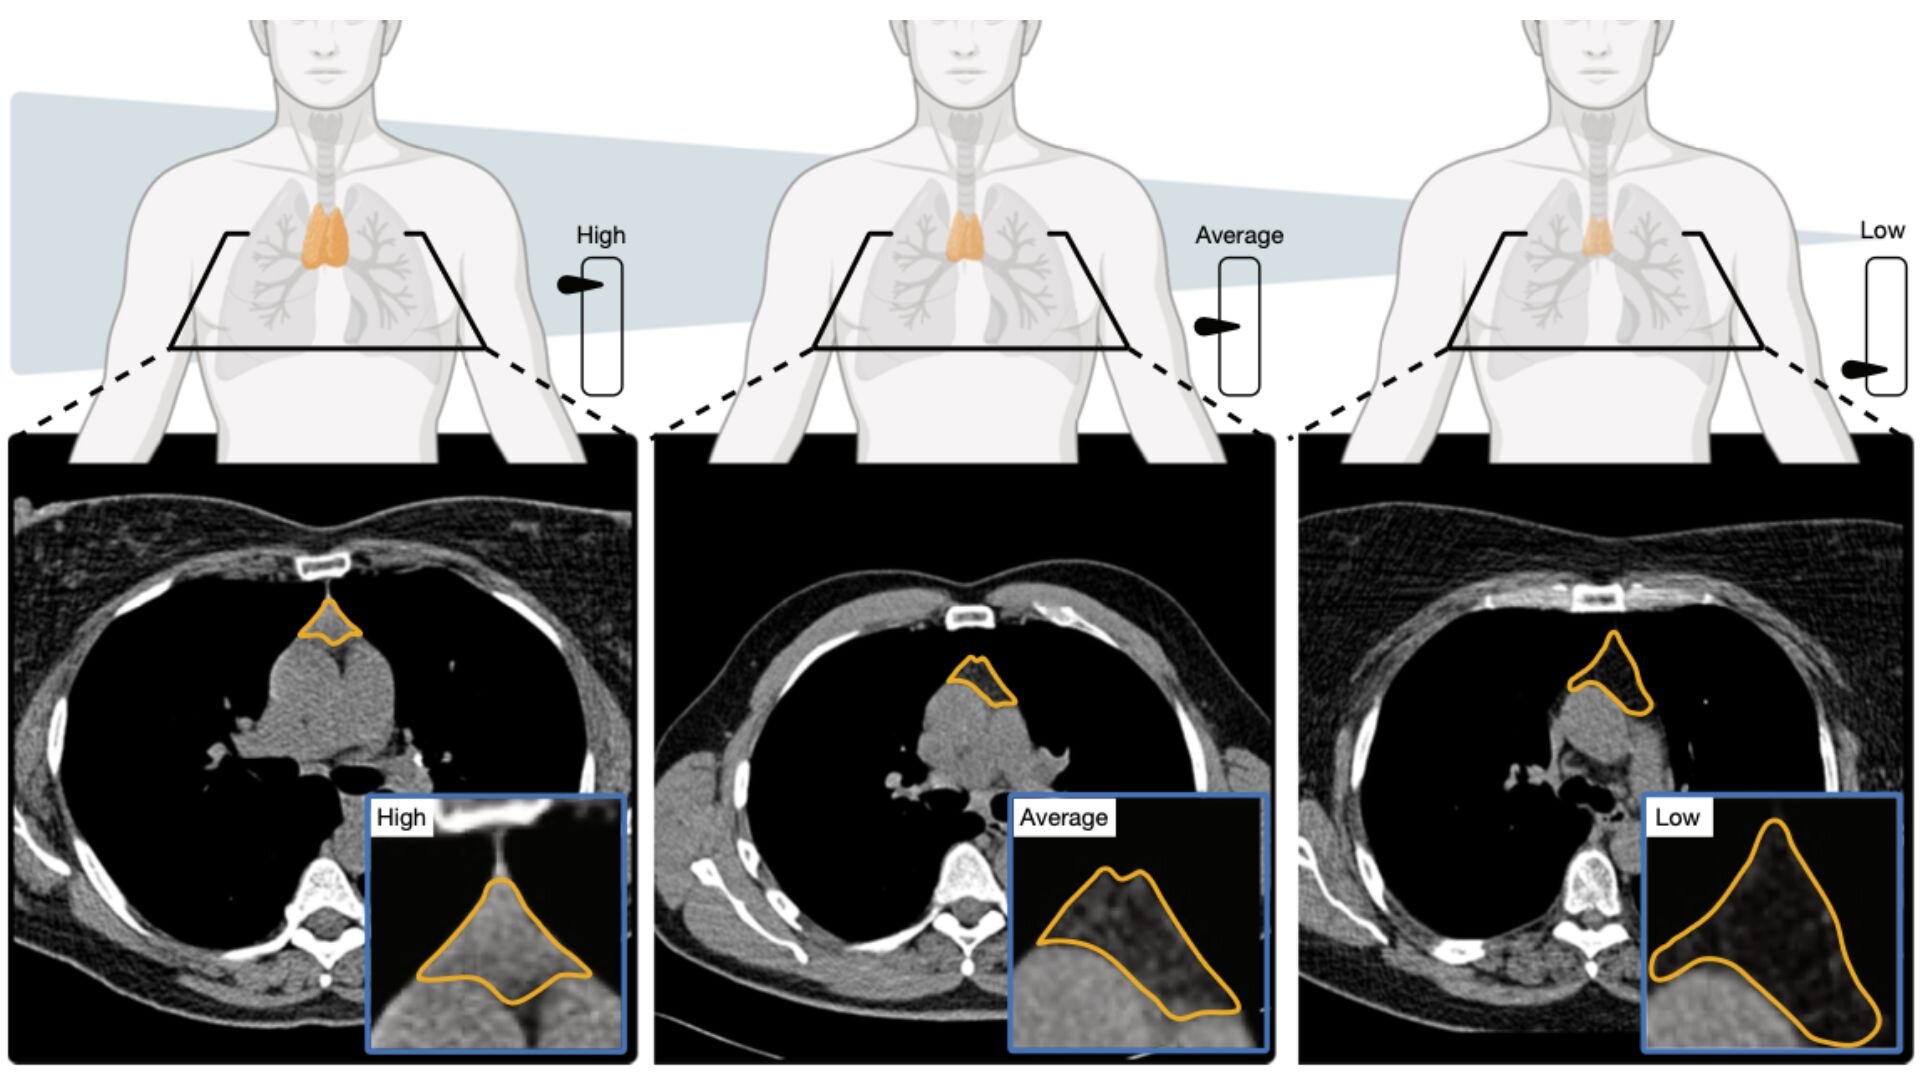

Yapay Zeka Timus Sağlığını Nasıl Ölçtü?

Araştırmacılar, binlerce kişinin BT taramalarını analiz eden bir yapay zeka modeli geliştirdi. Bu sistem, timusun yapısını ve dokusunu inceleyerek kişiye özel bir "timus sağlığı puanı" oluşturdu. Geniş ölçekli veri analizi sayesinde timusun görünmeyen etkileri ilk kez bu kadar net ölçülebildi. Çalışma, 25 binden fazla kişi üzerinde yürütüldü ve geniş ölçekli veri ile desteklendi.